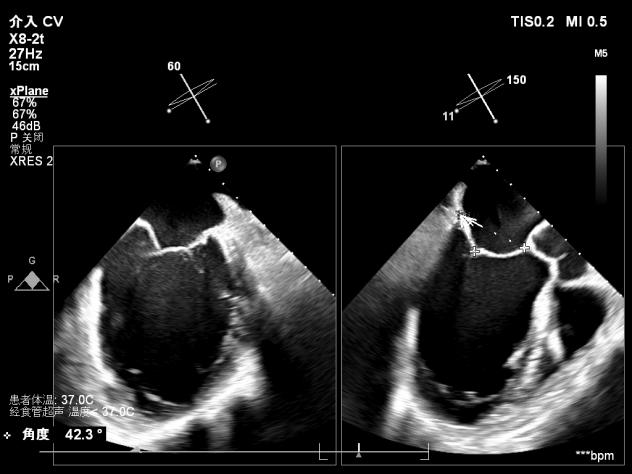

【术前超声心动图提示】

室性功能性二尖瓣反流(混合性MR),重度(MR 5+),反流位于2区–3区,左室射血分数低(EF27%)

【瓣膜与功能特点】

前超声评估明确关键指标:二尖瓣瓣环呈扩张状态(前后径约3.3cm,瓣环面积约4.75cm²,前叶长约2.1 cm,后叶长约1.4 cm),瓣叶增厚且后叶栓系明显,前后叶对合不良;同时伴左房、左室明显扩大,左室收缩功能显著减低,合并节段性运动异常。经团队综合评估,该患者为“多支冠脉支架植入后+低射血分数+重度功能性二尖瓣反流(混合性MR)”的高危病例,左室射血分数(EF)仅20%,在接受GDMT药物优化治疗6周后EF值提升至27%,但症状仍无法有效缓解,遂决定为其实施经心尖入路二尖瓣缘对缘修复术(TA-TEER)。

【术中操作(含关键步骤超声)】

鉴于患者术前心功能差、多支架植入的特殊情况,手术全程需兼顾“精准操作”与“保护心功能”双重要求:在全麻与经食道超声的协同引导下,团队先突破心功能受损导致的术野稳定性难题,稳步经心尖建立手术轨道与输送鞘;随后聚焦二尖瓣2偏3区精准置入一枚Ⅱf型夹合器,成功攻占这一解剖位置深、毗邻结构敏感、容错率极低而操作难度陡增的区域。